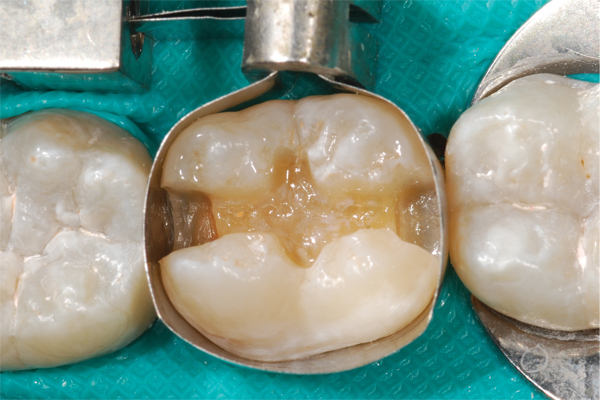

(2.) Preparation of tooth No. 31.

Figure 2

Higher viscosity bulk-fill composites can be used up to the occlusal surface, however. Two clinical cases using the bulk-fill composites Tetric EvoCeram Bulk Fill and SonicFill are presented in Figure 2 through Figure 6. Limitations when placing a high-viscosity bulk-fill composite include difficulty of condensing and esthetic restraints. Condensing a high-viscosity resin composite ensures adequate adaptation to the tooth preparation and sufficient interproximal contacts. Condensing 4 mm of composite is more difficult than condensing 2 mm. To ensure adequate interproximal contacts, a sectional or circumferential matrix with an inciso-gingival curvature can be used to obtain a tight area of contact gingival to the marginal ridge. A ring should be used to help separate the teeth and improve the tightness of the contact area.